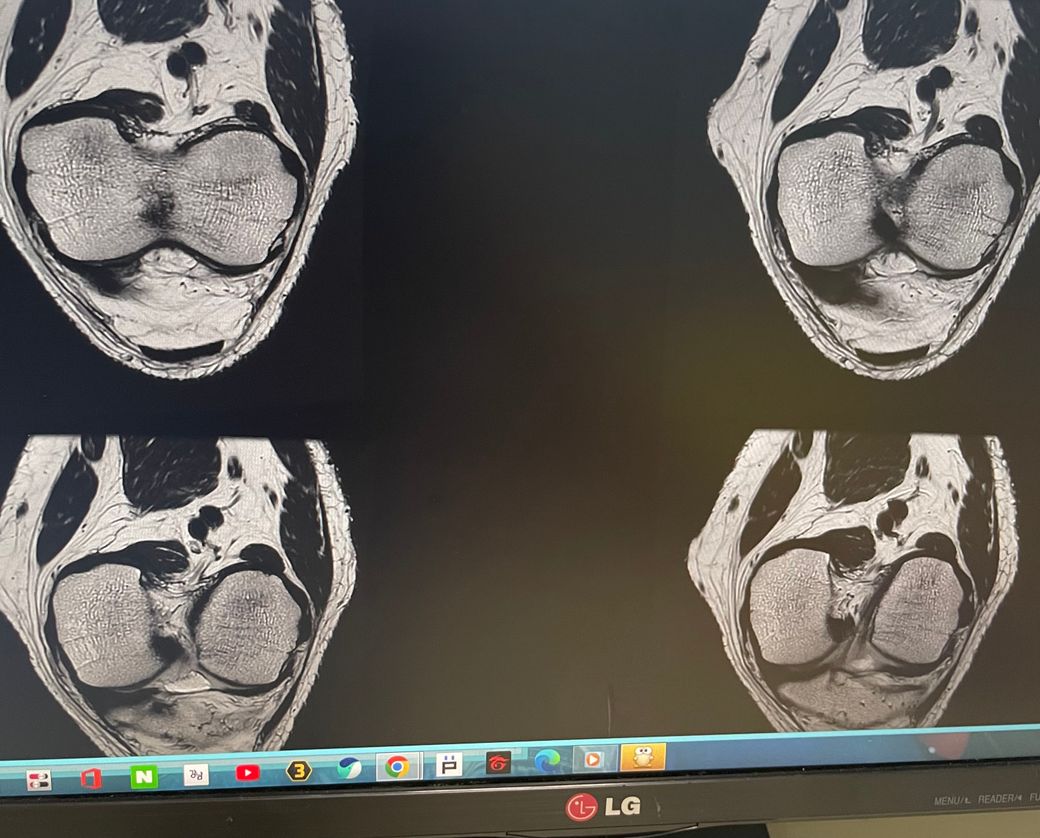

무릎 왼쪽 mri 사진 판독 부탁드리겠습니다.

안녕하세요 3달전쯤에 무릎을 다쳐서 약 한달전에 mri를 찍었습니다.

현재 판독상 인대나 반월연골 손상은 없는 것으로 판독지에 기재되어 있습니다. 임상적인 증상도 중요하니 담당의사와 상의하시고 신검시에 해당과 군의관 판정을 받으시는 것이 좋겠습니다.

십자인대에는 문제가 없지만 반월판의 문제가 있는 것으로 보입니다.

ACL 즉 전방 십자 인대에 불규칙한 소견은 있으나 Tear 즉 십자 인대가 파열되었다는

소견은 관찰되지 않는 상태이며 연골에 퇴행성 변화는 있는 것으로 보이나 이 역시 R/O

으로 확실하지 않음을 의미합니다. 결과적으로 십자 인대의 파열이 명확하지 않는 상태로

군대를 연기할 사유가 될지는 모르며 전방 십자 등 인대 손상의 경우는 명확하게 파열된

소견을 보이지 않는 경우, 군 입대에 문제가 되지는 않을 것으로 생각됩니다.